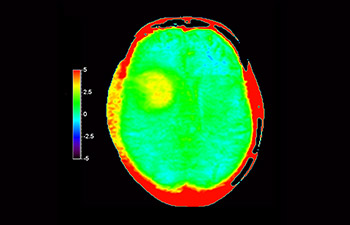

Glioblastoma

Brain with glioblastoma

with 3D APT